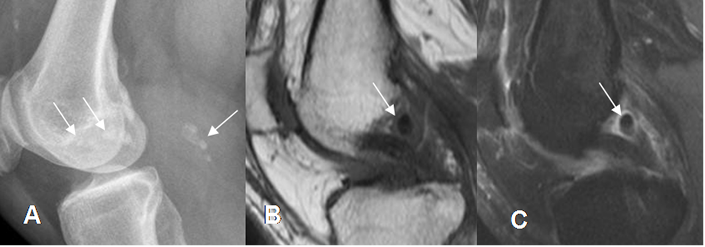

En la RM hay derrame articular, con cuerpos libres calcificados o no. Los calcificados presentan ausencia de señal y los no calcificados, tienen SI similar a la medula ósea. (19). (Fig 71, 72 y 73).

Fig 71. Condromatosis sinovial.

A: Rx lateral. Calcificaciones en la región intercondilea y parte posterior de la rodilla.

B: RM sagital en T1 y C: RM sagital en STIR. Cuerpo libre calcificado, hipointenso en ambas secuencias.